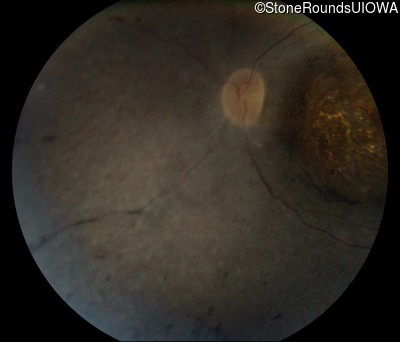

Fundus Photography - Right - Light Perception

Exemplar